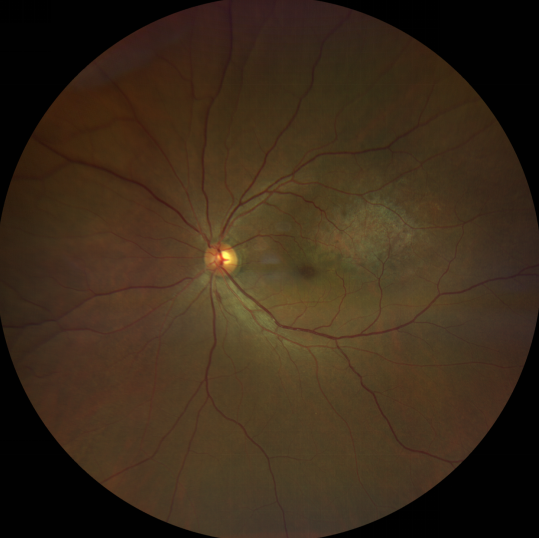

脈絡(luò)膜黑色素瘤患者在發(fā)病早期無眼痛等癥狀,當(dāng)腫瘤較小時(shí)較難發(fā)現(xiàn),隨著病程進(jìn)展,腫瘤增大,發(fā)生滲出性視網(wǎng)膜脫離或累及黃斑,視力下降才就診。

脈絡(luò)膜黑色素瘤惡性程度高,50%的患者會(huì)發(fā)生轉(zhuǎn)移,轉(zhuǎn)移到肝、肺等遠(yuǎn)處臟器,常見的轉(zhuǎn)移方式是經(jīng)鞏膜導(dǎo)管擴(kuò)散,經(jīng)視神經(jīng)蔓延者罕見。一旦發(fā)生轉(zhuǎn)移,1年生存率只有10%,即絕大多數(shù)病人在半年至1年間會(huì)失去生命。因此,早期診斷和選擇合適的治療方式對有效提高局部腫瘤的控制率、降低腫瘤的遠(yuǎn)處轉(zhuǎn)移率、延長患者的生存率具有重要意義。